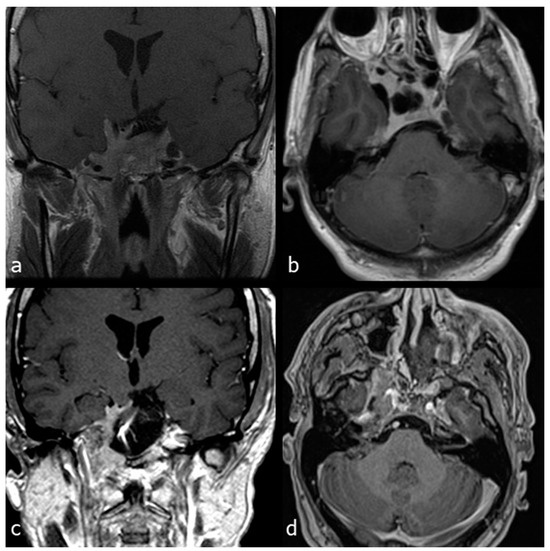

- Case 1